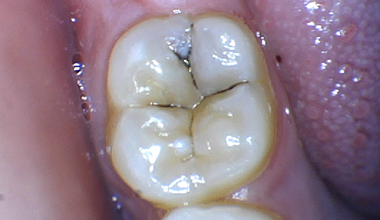

인레이

충치치료 CASE

CASE 01

치료 전 -

치료 중 -

치료 후